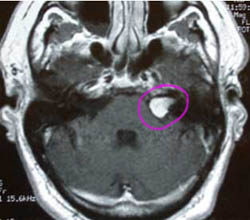

Невринома на МРТ головного мозга.